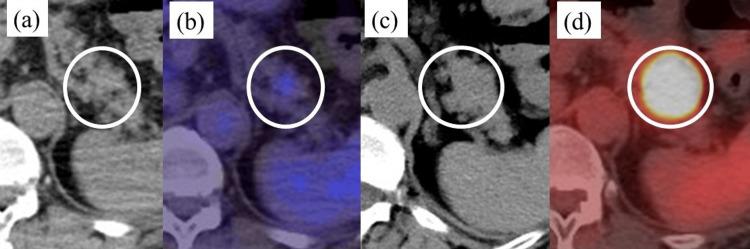

Cancer (including pancreatic cancer) can develop following a infection within one year of tuberculosis infection. However, it is unclear whether tuberculosis infection increases the risk of developing adenosquamous carcinoma of the pancreas (ASCP), an extremely rare cancer with a poorer prognosis than pancreatic ductal adenocarcinoma (PDAC). Herein, we report a case of rapid growing ASCP discovered upon a resection for neck tuberculous lymphadenitis. The patient was a 57-year-old woman. An excisional biopsy of the swollen right neck lymph nodes revealed tuberculous lymphadenitis. One month after the biopsy, an abdominal computed tomography scan showed a 2.0 cm (diameter) ischemic tumor in the pancreatic tail. The tissue obtained using endoscopic ultrasonography-guided fine-needle aspiration led to the pathological diagnosis of ASCP. Two months after the biopsy, the tumor had grown to 3.5 cm (diameter), and invasion of the stomach and colon was suspected. Distal pancreatectomy, splenectomy, partial gastrectomy, and transverse colectomy were performed. The final diagnosis was ASCP (4.7 cm, pT3, pN0, cM0, and pStage IIA). Postoperative adjuvant combination chemotherapy combined with antituberculosis drugs was administered orally. We report the first case of rapidly growing adenosquamous carcinoma resected from the pancreas in association with tuberculous lymphadenitis. Additional evidence is needed to confirm that tuberculosis infection increases the risk of developing pancreatic adenosquamous cell carcinoma because its potential role in promoting squamous metaplasia is unclear.

摘要